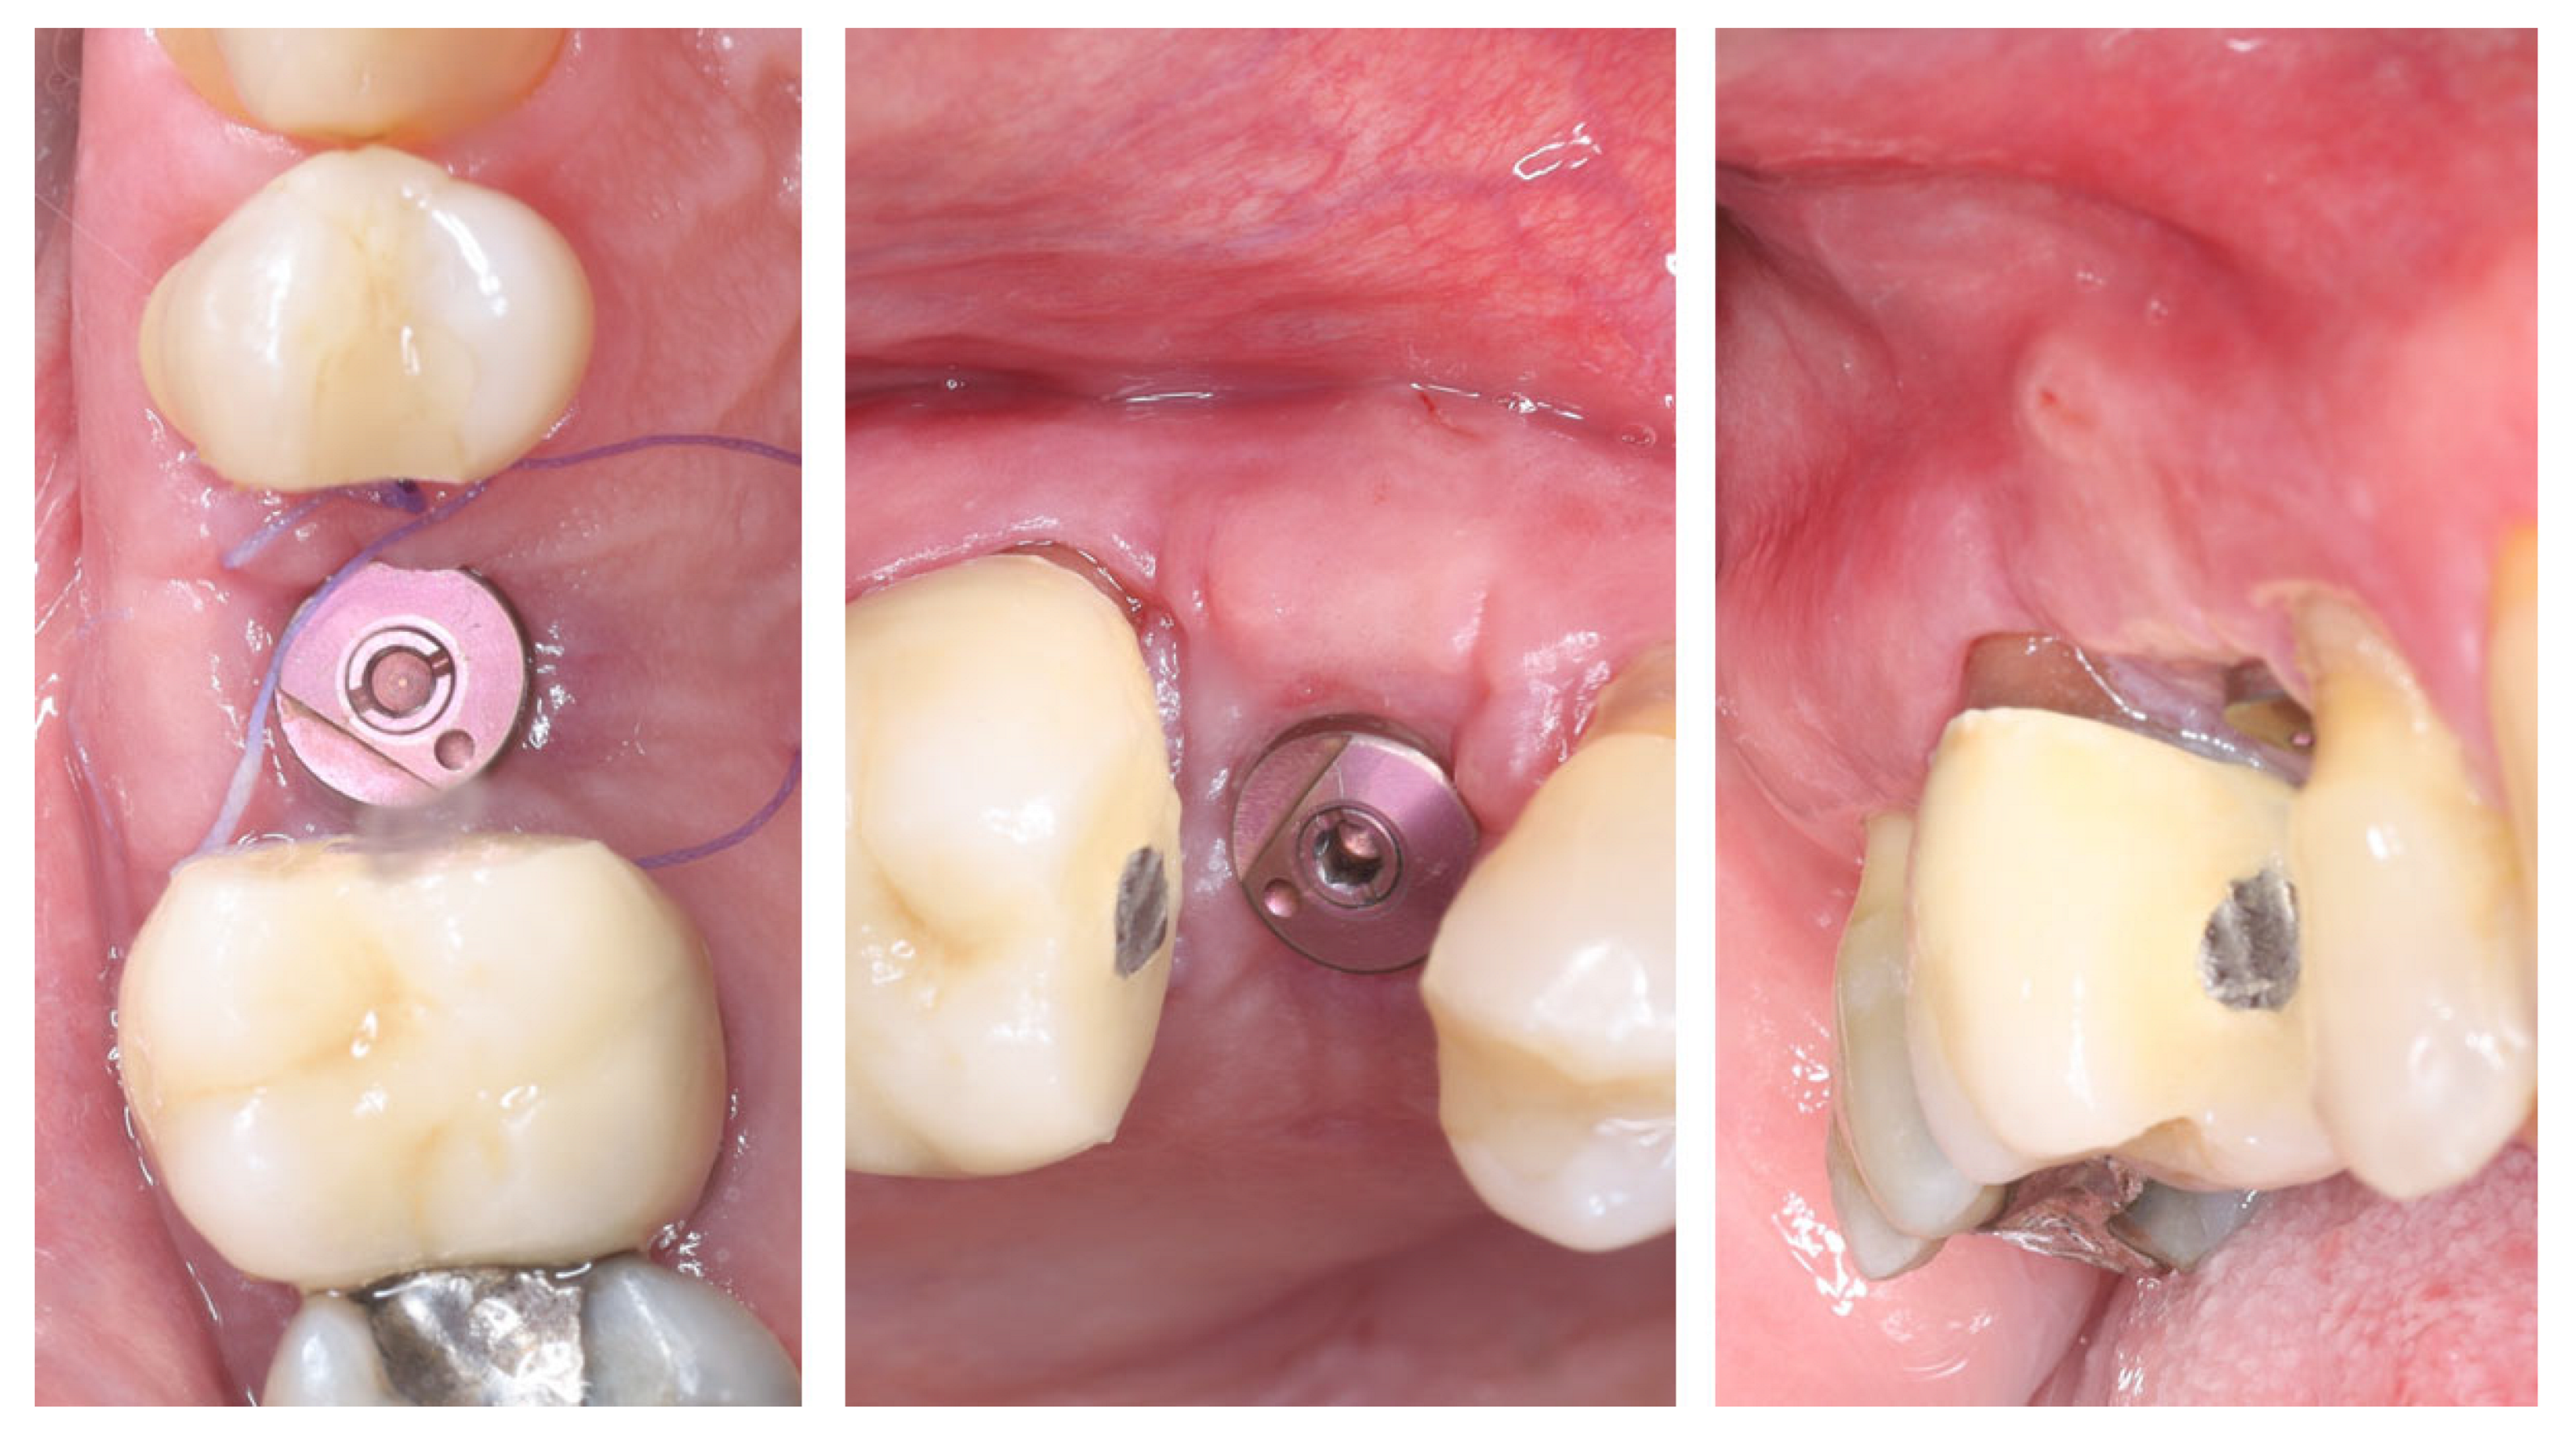

2. Materials and Methods—Clinical Case